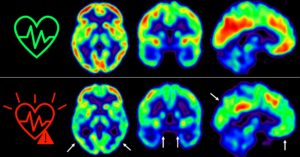

Las enfermedades cardiovasculares y la demencia coexisten en etapas avanzadas en muchas ocasiones; sin embargo, hay pocos estudios longitudinales en personas de mediana edad, 50 años, que hayan evaluado la interacción entre la aterosclerosis y sus factores de riesgo sobre la salud del cerebro. Ahora, una investigación realizada en el Centro Nacional de Investigaciones Cardiovasculares […]